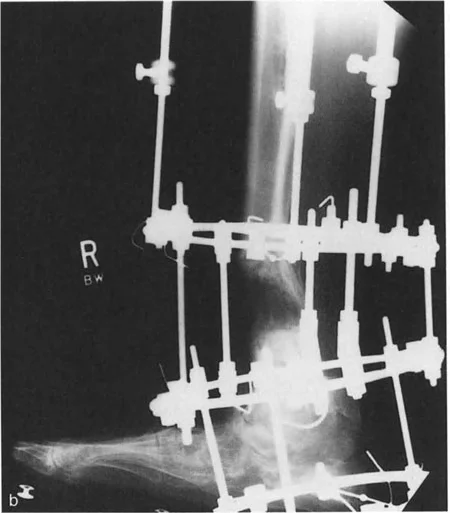

أنواع جراحات قطع العظم فوق الكاحل (Supramalleolar Osteotomy)

جراحة قطع العظم فوق الكاحل (SMO) هي الإجراء الأكثر شيوعًا لتصحيح تشوهات قصبة الساق البعيدة. تتضمن هذه الجراحة قطعًا دقيقًا في عظم الساق (القصبة) فوق مفصل الكاحل مباشرة، ثم إعادة محاذاة العظم وتثبيته في الوضع الصحيح. هناك عدة أنواع من هذه الجراحة:

3. قطع العظم القوسي البؤري (Focal Dome Osteotomy):

• يتم عمل قطع منحني في العظم، مما يسمح بتصحيح